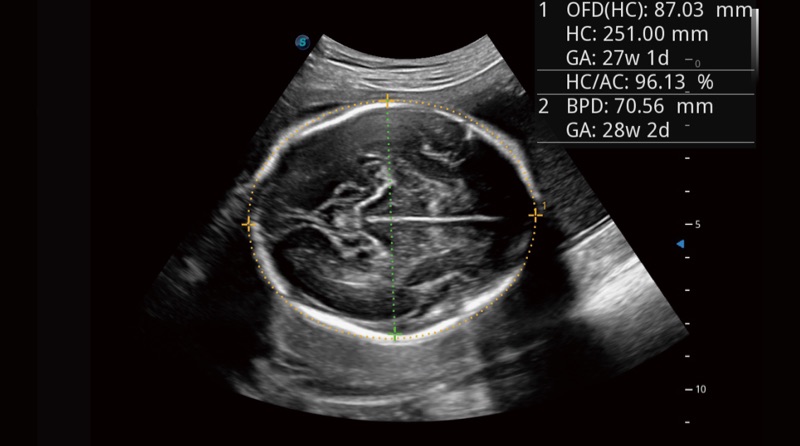

„Auto OB Plus

Greita ir labai efektyvi vaisiaus biometrija atliekama naudojant „Auto OB“. Tuo tarpu šio giliuoju mokymusi pagrįsto metodo teikiami nuoseklesni rezultatai gali veiksmingai sumažinti nuo vartotojo priklausantį kintamumą.